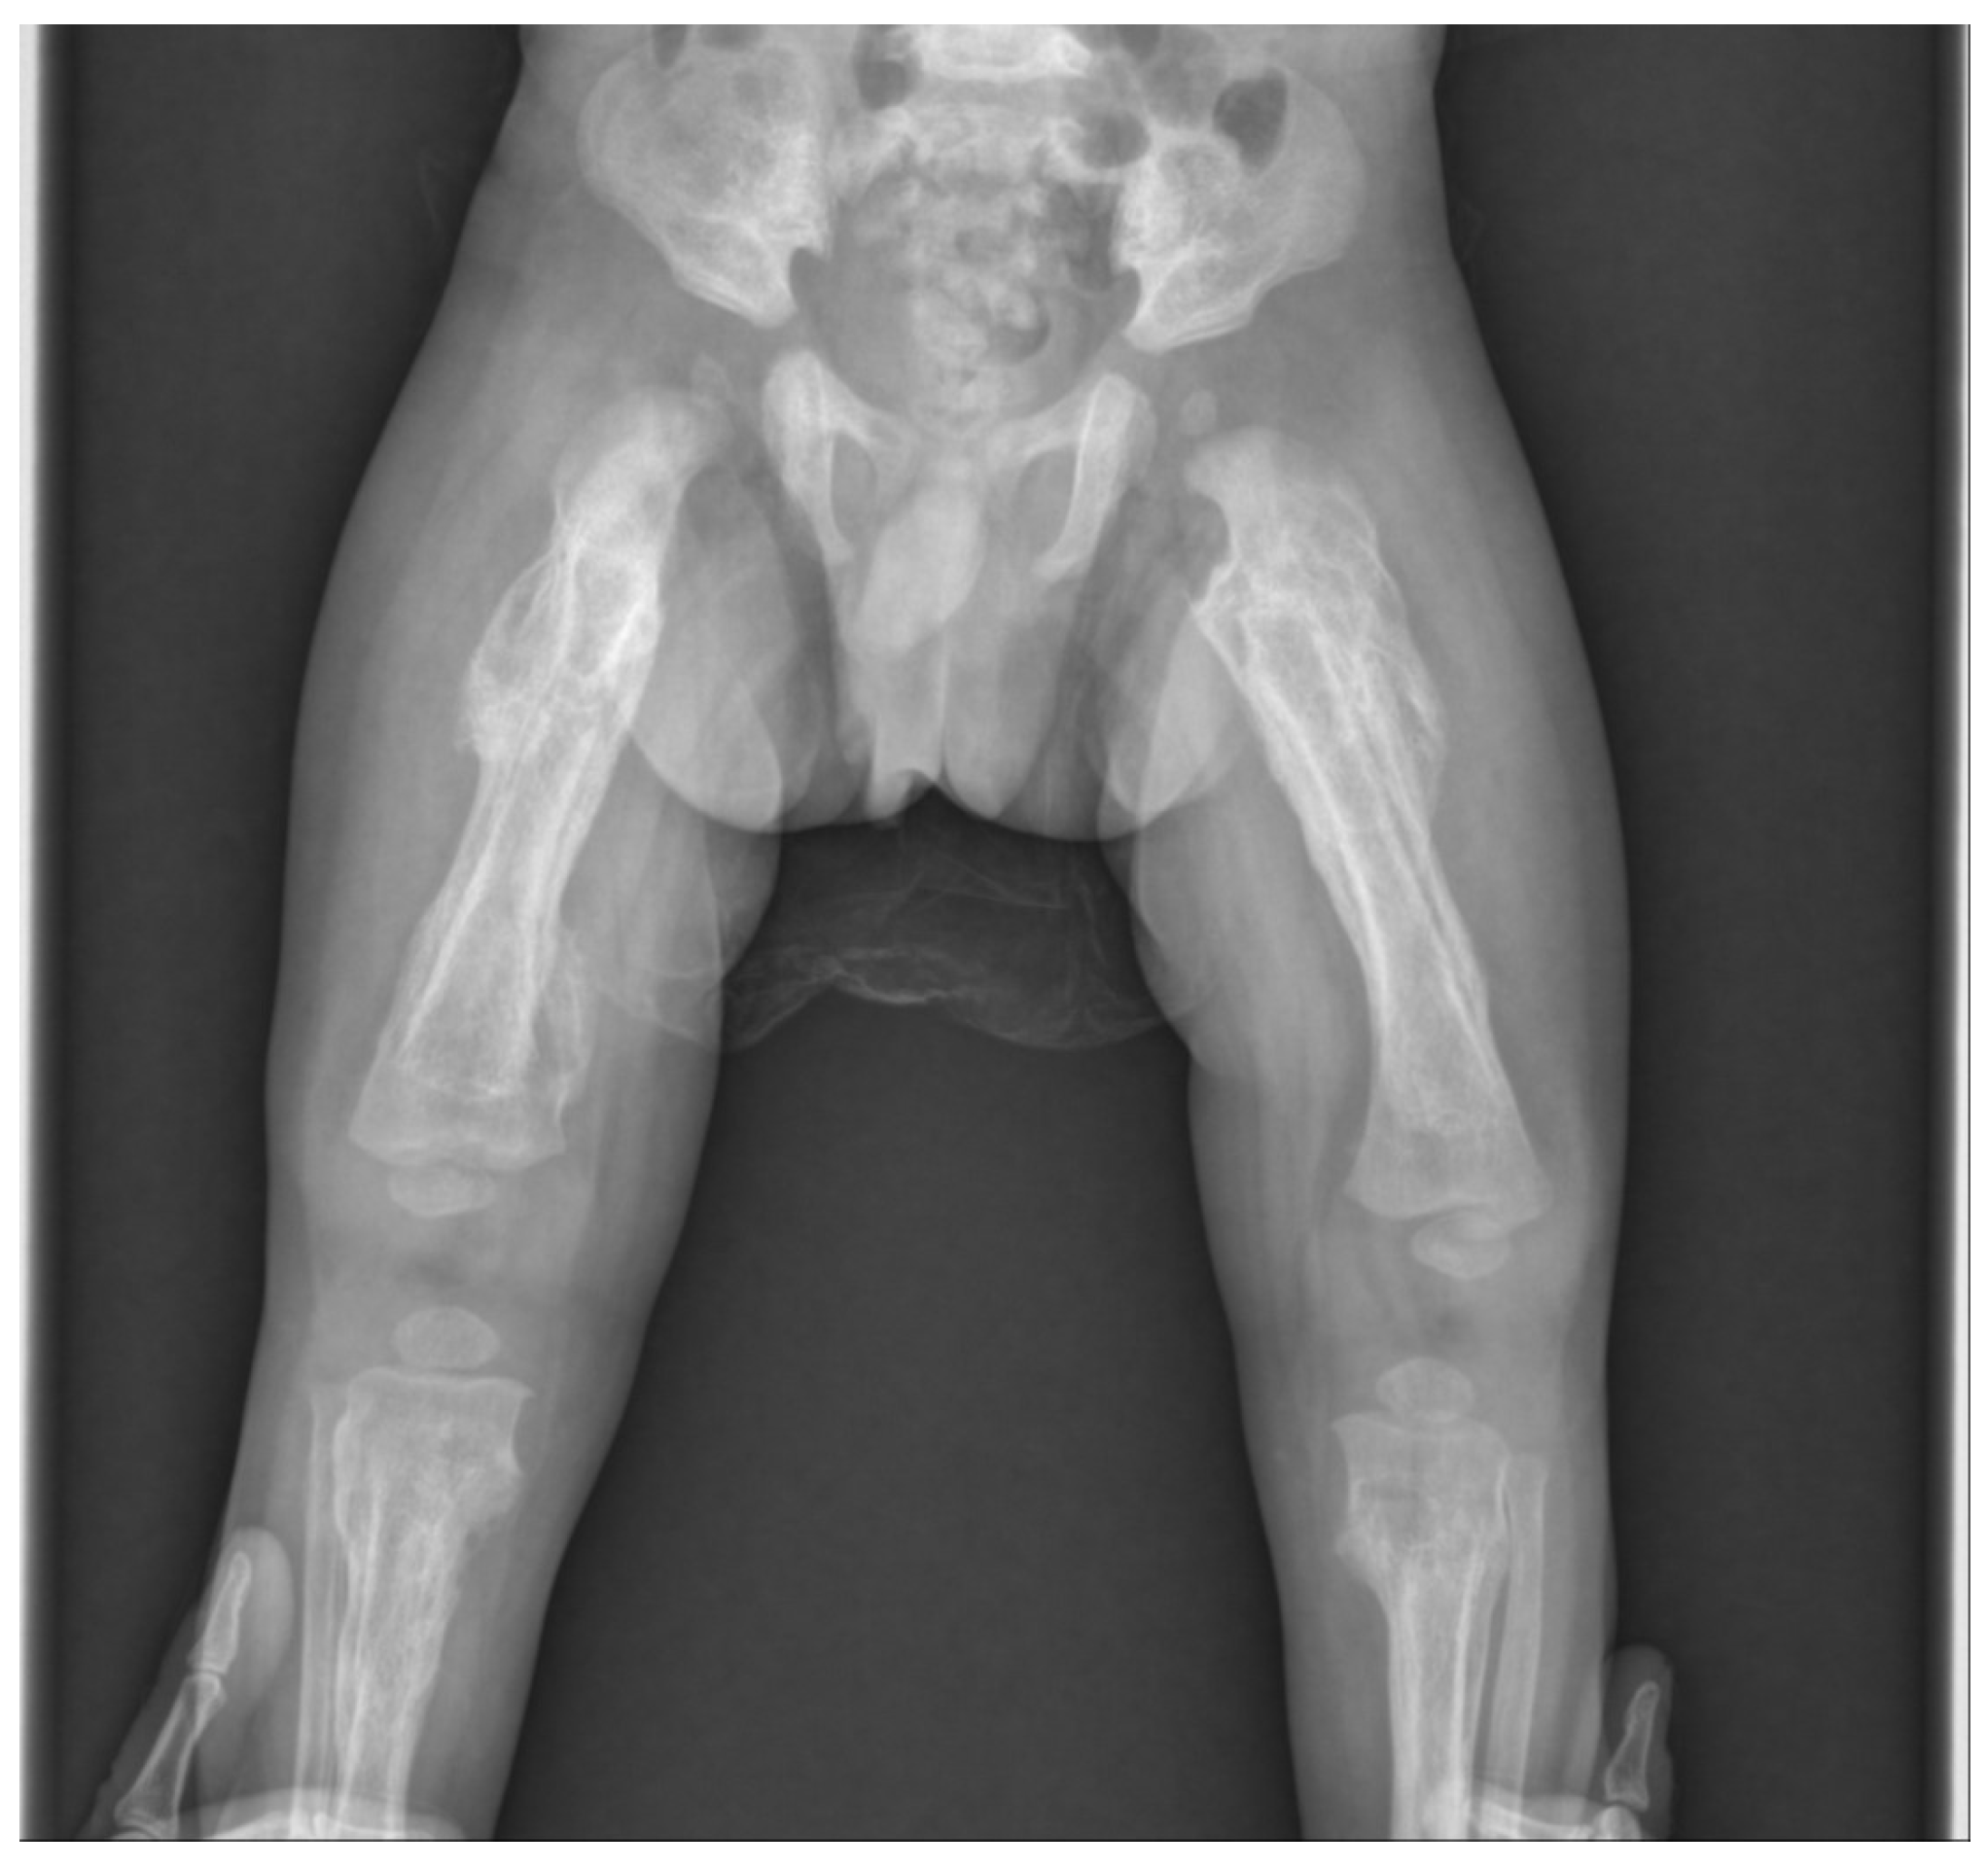

Therefore, we suspected child abuse based on the following clinical and radiological features: multiple fractures present in an infant under 18 months of age without any history of major trauma, femoral fracture in a nonambulatory infant, and hyperostosis involving epiphysis rather than diaphysis. The patient was found to be a victim of child abuse through a police investigation, and three months have passed since then, and the fracture has improved (Figure 4). Because it was concluded that it was parental child abuse, we learned that child abuse should not be excluded from the visible parental actions of caring for a child.

However, in the present case, neither the mandible nor the skull were invaded, there was a tendency for epiphyseal rather than diaphyseal invasion of long bones, and extensive cortical disruption; therefore, we diagnosed the findings as child abuse-related fractures. Although rib fractures and abdominal injuries were also suspected after expert inspections, no abnormalities were found. There were, however, multiple fractures, including clavicle fractures, that were identified, but all were possible to manage with conservative treatment. Conservative treatment using a simple splint was thus performed, and complete union and remodeling findings were observed after 3 months. The patient is now isolated from his parents and is being treated in a shelter. The three-month follow-up was the last at our hospital. Our case study, therefore, emphasizes that clinicians must obtain a detailed history and perform a thorough examination. Before diagnosing a child of maltreatment, medical conditions that resemble child abuse should be fully evaluated. However, the presence of metabolic bone disease may not exclude the possibility of concurrent child abuse. The clinician’s role is not only in prevention and early detection but also in continuing to care for and manage the child and the family.

Figure 4. After 3 months, radiographical findings showed that the fracture was healed and remodeled.